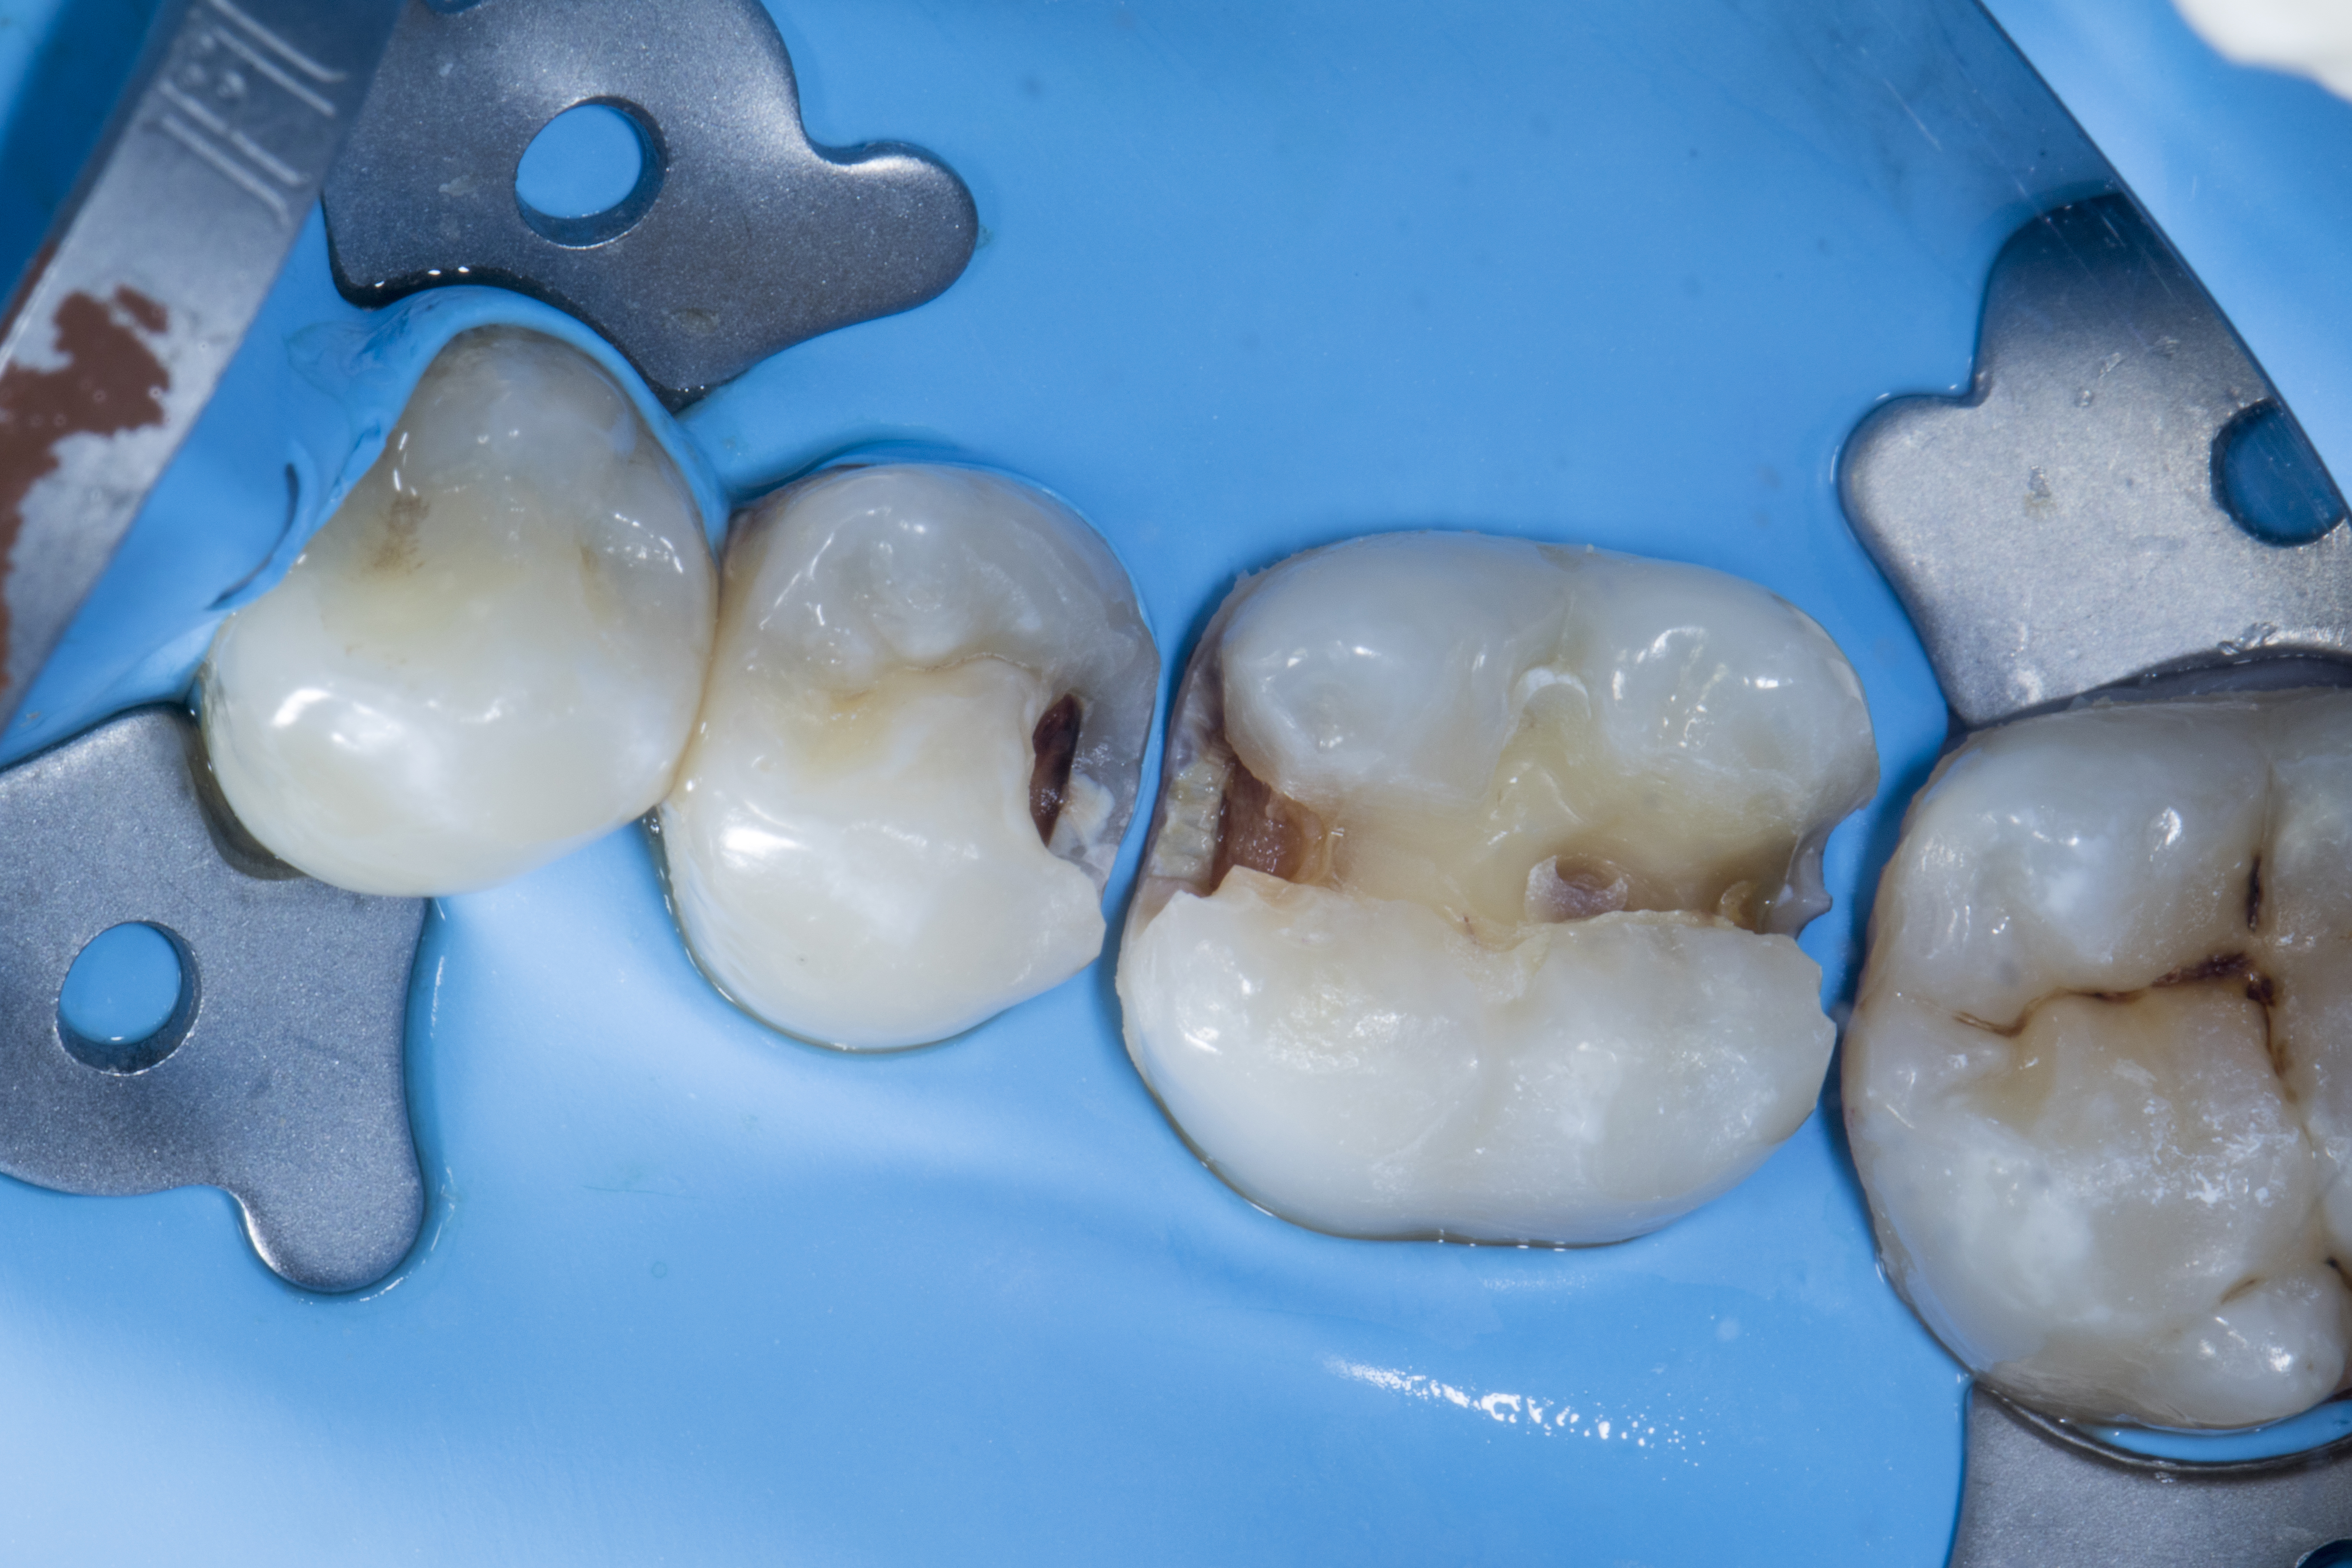

A 25 Years old male patient visited the clinic with a carious lesion on tooth #35 distally and #36 both mesially and distally. Tooth # 36 shows old composite restoration. The patient complains of sensitivity in the 35-36 region when exposed to cold or sweet.

Figure 1

Figure 1. A carious lesion on tooth #35 distally and #36 both mesially and distally. Tooth #36 shows old composite restoration.